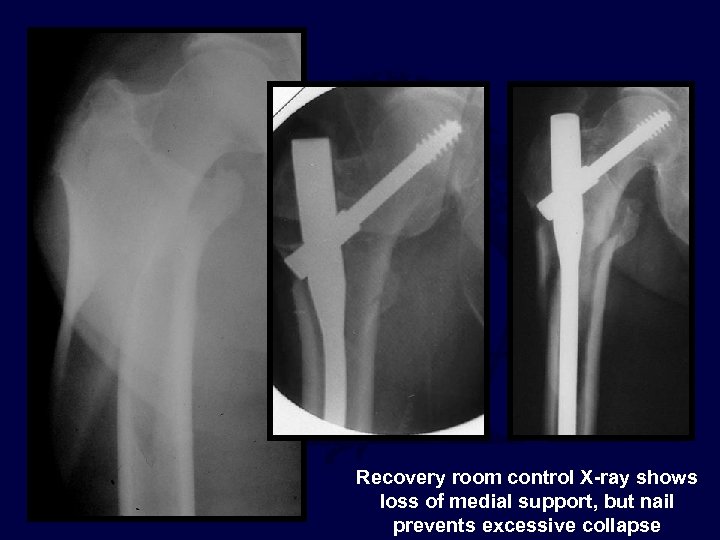

Recovery room control X-ray shows loss of medial support, but nail prevents excessive collapse